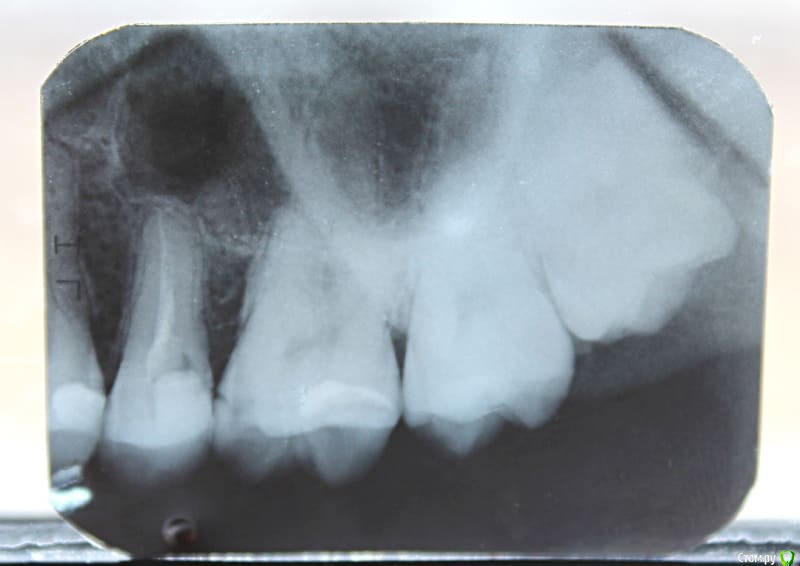

annie23 Опубликовано 11 июня, 2018 Поделиться Опубликовано 11 июня, 2018 Добрый день! Нужна ваша консультация. В январе этого года пролечила пульпит 15 зуба. В какой-то момент он начал реагировать на холодное/горячее, сейчас такого не наблюдается. Изредка где-то далеко чувствую тянущую боль (но это скорее я придираюсь). Что беспокоит на данный момент: 1. Кажется, что внутри забыли что-то инородное (как будто много пломбировочного материала наложили). Один из стоматологов чуть-чуть прошлифовал пломбу, но это ощущение все равно сохраняется.2. Запах от зуба. Он, простите, зловонный (точно такой же как до лечения), особенно это ощущается после чистки зубной нитью. Снимков до пломбировки канала нет, лечила в государственной. После была у двух частных стоматологов, оба развели руками и сказали, что все нормально. Скажите, с этим нужно научиться жить или с этим можно что-то сделать?! (И еще у меня были подозрения на кисту, но никто об этом не упомянул) Ссылка на комментарий

red_butler Опубликовано 11 июня, 2018 Поделиться Опубликовано 11 июня, 2018 Пятый, перелечить корневые каналы и протезировать искусственной коронкой, на шестом лечить кариес на боковой поверхности. 1 1 Ссылка на комментарий

St. Опубликовано 11 июня, 2018 Поделиться Опубликовано 11 июня, 2018 По снимку от зуба осталось не так много и есть большой риск сломать его в будущем. Коронка защитит от этого Ссылка на комментарий